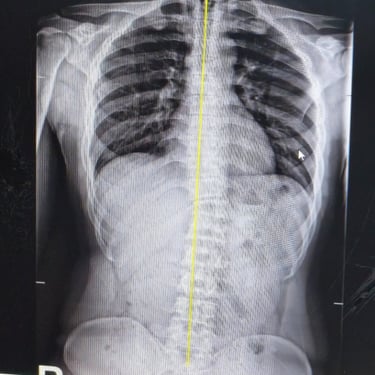

Gallery

Provide a short description of the gallery, highlighting key things.